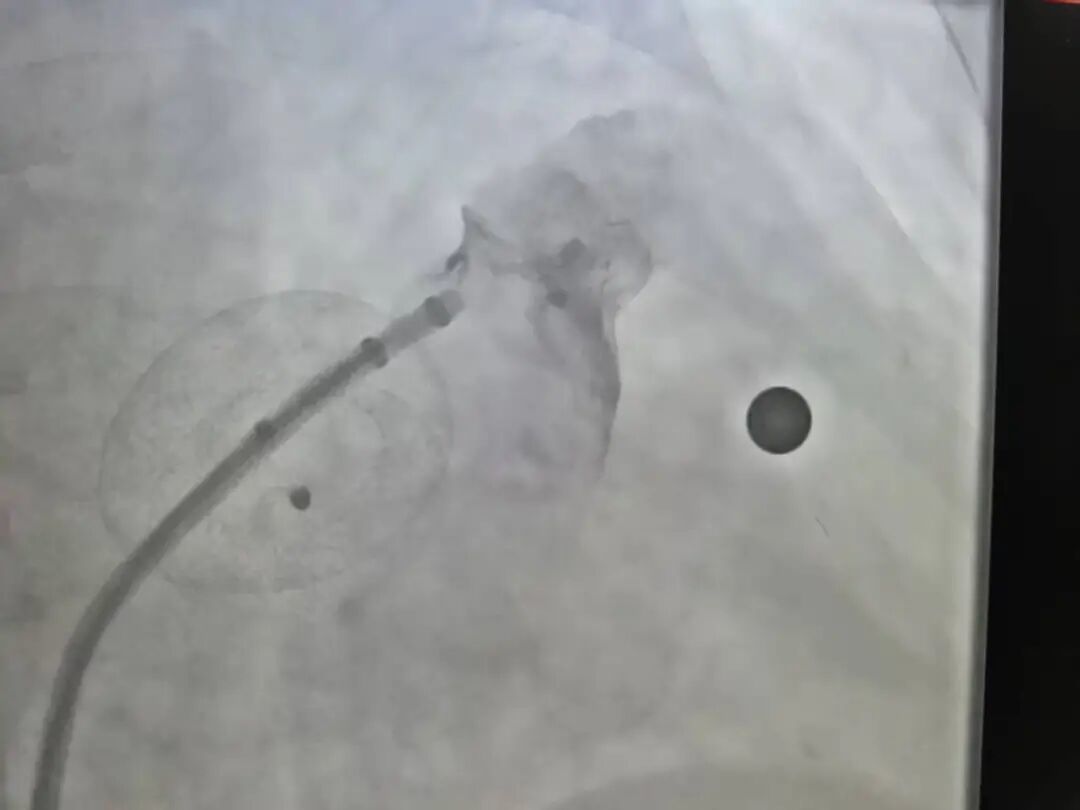

这仅是第一步。随后,团队运用冠脉介入中的微小球囊扩张技术,像打造精密模具般,沿着细若游丝的导丝路径,将通道逐步、可控地扩张,最终构建起一条足以输送大型鞘管与左心耳封堵器的安全“轨道”。

成功建立一条轨道并成功植入左心耳封堵器

这一系列操作,堪称介入医学中“以柔克刚、循序渐进”的典范。最终手术圆满成功,李伯术后恢复状态良好。